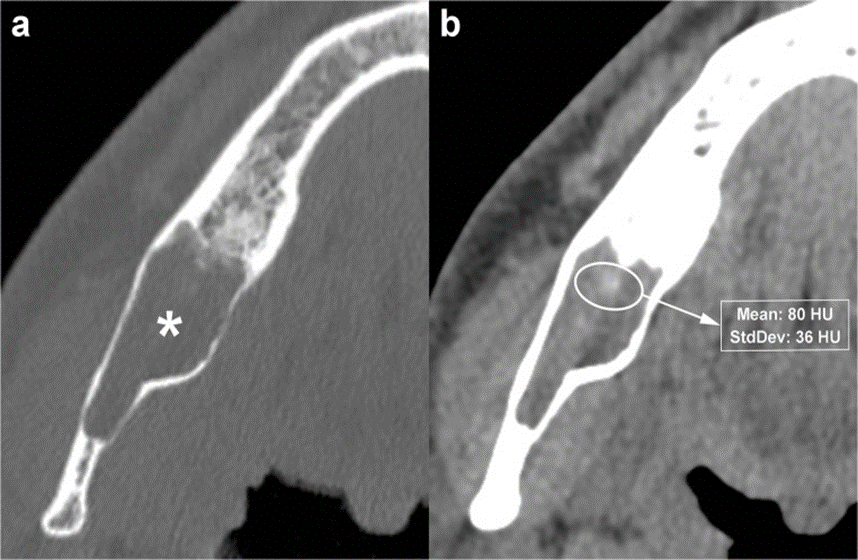

The main advantage that makes CBCT a particularly attractive technique in the evaluation of maxillary and mandibular lesions is its higher spatial resolution compared with MDCT. Conversely, the main disadvantage of CBCT is the poor contrast resolution, which is not suitable for soft tissue contrast discrimination. Hence, CBCT is not able to evaluate the extension into soft tissues and precludes the possibility of contrast medium injection [31]. In the assessment of an OKC, CBCT is considered more effective to demonstrate the bony changes of the cortical plates of jaws (buccal, palatal or lingual cortices), whereas MDCT is more effective at evaluating internal density and extension into soft tissue.

Internal high-density areas are frequently found and reflect the presence of keratinised material within the OKC (Fig. 12) [14]. This peculiar internal feature is detectable mainly on MDCT scan due to its better soft tissue contrast discrimination compared to CBCT scan (Fig. 12). Although rare, calcifications may occur within OKCs; this finding is mostly observed in histological examinations (Figure. 13). Finally, at MDCT, the OKCs typically do not show enhancement after contrast administration [32].